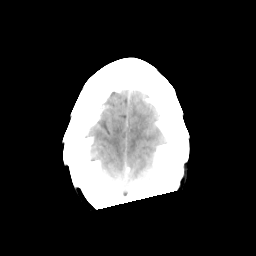

Sarcoma: Roentgen-ray CT -- Slice #22

[Home][Help][Clinical] Slice 22